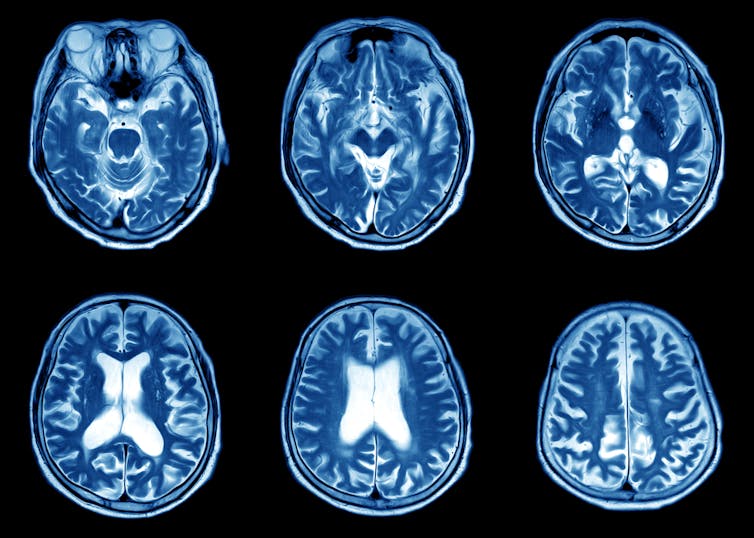

Magnetic resonance imaging (MRI)

MRI uses a combination of a powerful cylindrical magnet and radiofrequency waves to generate an image of the body. It’s quite loud and patients must be wearing suitable hearing protection devices such as earplugs or headphones (where relaxing music can be listened to).

Patients normally lie within the magnet cylinder, and a frame (which works like an antennae) is placed around the body area needing to be imaged, as close as possible, so the maximum possible signal can be detected in order to reconstruct highly detailed images.

Our body contains hydrogen, so a radiofrequency is transmitted into the body at the frequency that will cause hydrogen atoms to oscillate. When the radiofrequency is switched off, the hydrogen atoms continue to oscillate and the frequency of this oscillation is detected by the frame or antennae.

The radiofrequency causes a voltage signal in the antennae, which is identified as an electrical signal. This is then digitised and an image is reconstructed using complex mathematical calculations.

Safety is paramount for patients having an MRI scan, and all patients must complete a safety questionnaire first to ensure they’re compatible with the imaging environment. The safety questionnaire asks if patients have any implanted metal objects such as pacemakers or infusion pumps or similar medical devices. This is because certain metal objects can cause harm to patients or staff if they enter the MRI environment because of the powerful magnet.

The most common application of MRI is imaging the brain with conditions that relate to neurology or neurosurgery.